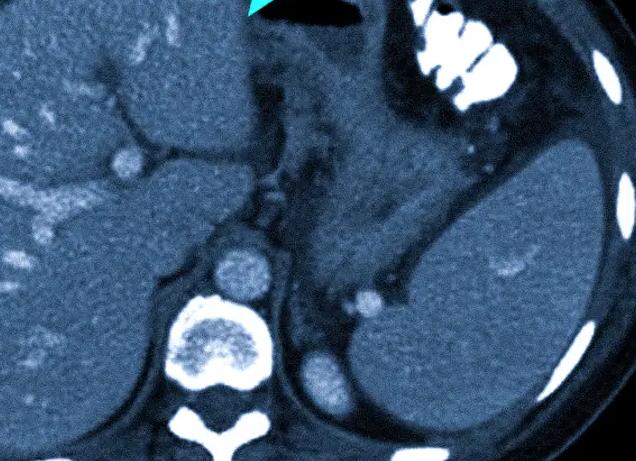

Нелегко выбрать, что лучше — КТ или МРТ коленного сустава, поскольку эти процедуры базируются на различных физических явлениях. Вместе с тем, в основе обеих методик лежит принцип томографии, согласно которому целевой участок тела подвергается послойному сканированию с последующим его воссозданием на дисплее в виде серии пошаговых срезов.